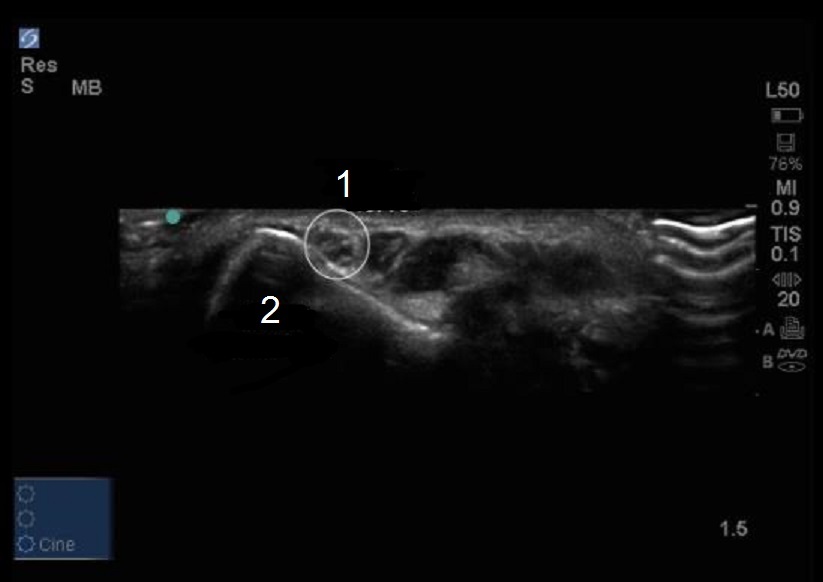

Elbow Cubital Tunnel Transverse 2 Image

Ulnar Nerve

Medial Epicondyle